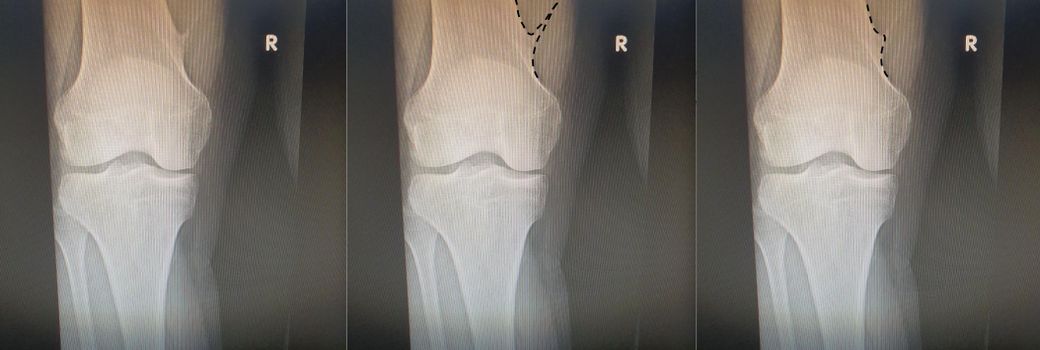

X-ray를 보시고 연골종 모양을 확인해주실 수 있으실까요?

어느날 무릎을 만지다가, 왼쪽 무릎에는 없는 무언가 딱딱한 것이, 오른쪽 무릎에는 있는 것을 자각하였습니다.

해서 정형외과에 가서 확인해 보니 "연골종"을 진단 받았습니다.

진단해주신 선생님 말씀으로는, 그리 날카롭지 않은 모양이라 하셨습니다.

그런데 X-ray를 볼 줄 모르는 제 관점에서는 좀 날카로운 것 같아보입니다.

X-ray를 첨부드리오니, 제 연골종의 모양이 어떤 모양에 가까운지 확인 부탁드립니다.

이미지 중 좌측이 원본입니다. 중앙과 우측 이미지는 제가 한번 그려보았습니다.

혹시 우측 이미지의 형태에 더 가깝다면, 원본에서 보이는 뾰족한 부분은 무엇이 찍힌 것인지 궁금합니다.

1. 아래 이미지의 좌측 원본을 보고, 연골종이 중앙과 우측 이미지 중 어느 것에 가까운지 설명. (보기와 같이 모양을 직접 그려주시면 더 좋겠습니다. 감사합니다.)

2. 만약 연골종의 모양이 우측 이미지에 가깝다면, 원본에 하얀색의 뾰족한 모양은 무엇이 찍힌 것인지 설명.

중앙 이미지와 비슷해보이는것 같으나 화질이 구져서 확실친 않습니다. 제대로 평가를 하고 싶으시다면 MRI를 찍어보시는 걸 추천드립니다.

대부분의 연골종은 양성이나 ~1%의 확률로 악성 변화를 할수 있습니다. 영상의학적으로도 평가가 가능한데, 엑스레이로는 불가능하며 MRI를 찍어봐야 합니다. 결국에는 수술로 제거를 해야 치료가 되며, 수술 후 병리소견으로 양성 악성 판정이 확실히 나게 됩니다.